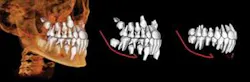

CBCT images can be modeled by Anatomage in the traditional form of digital study casts. They can then be viewed and morphed into desired tooth positions. The pre/post treatment CBCT scans can be superimposed showing the positional change between the two, which is actually 4D imaging (Figure 3). An animated, digital morph movie can be made to show the before and after morphing.

Anatomage is at the forefront of this "Dynamic CBCT" with its ability to superimpose two CBCT scans to visualize actual changes over time or projected changes with modeling simulations (Figure 4).